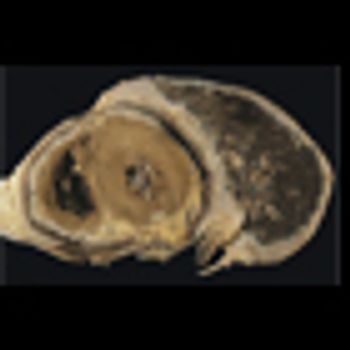

The NLST is a landmark trial demonstrating that implementation of low-dose CT screening lowers lung cancer–related mortality. We must put the study results and cost-effectiveness analyses in the context of the staggering statistics: up to 65% of lung cancer patients present with advanced-stage disease where treatments are often costly, toxic, and only palliative in nature.